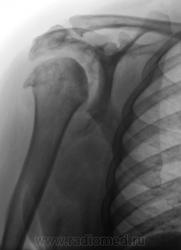

Где же подевался плечевой отросток лопатки? Что за мягкотканный компонент в подмышечной области? Костные разрастания само собой...это видно...

Если бы и конгруэнтность суставной поверхности плечевой кости была бы нарушена - предположил бы сирингомиелию...пока в раздумии, задачка не из простых....

Да патология весьма интересная. Мы долго ломали голову взвешивая все "ЗА", проводя диф. диагностику между сирингомиелией и волчанкой.

А для волчанки, такая картина, не характерна.